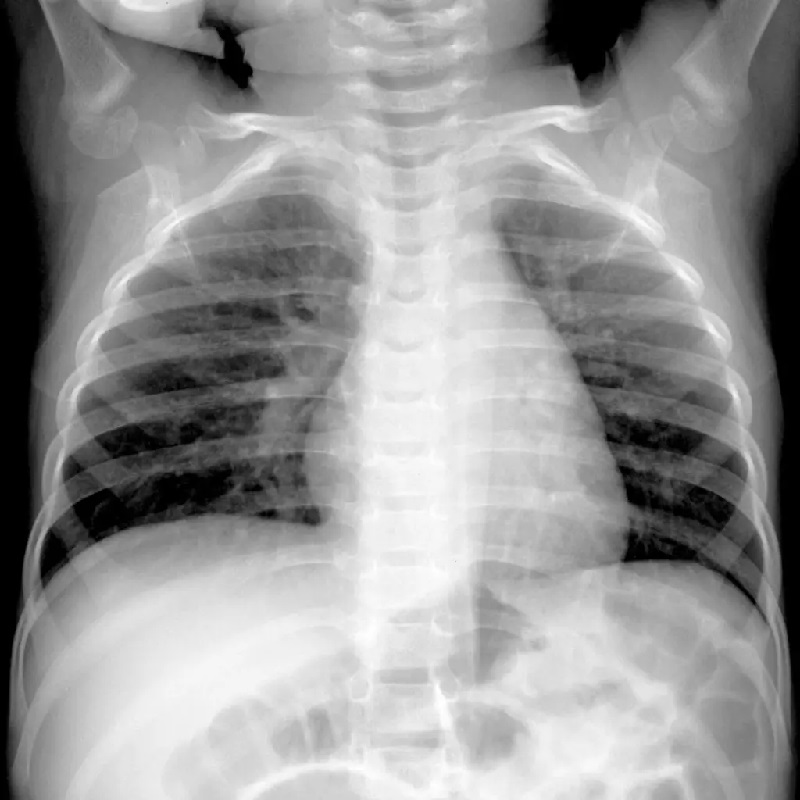

صورة بالأشعة السينية X-ray لطفل يبلغ من العمر 4 أشهر مصاب بفيروس ميتابنيوم البشري أو H.M.P.V. يمكن أن تؤدي الحالات الشديدة من المرض إلى التهاب الشعب الهوائية أو الالتهاب الرئوي، خاصة بين الرضع وكبار السن والأشخاص الذين يعانون من نقص المناعة

معظم حالات العدوى بفيروس HMPV خفيفة تشبه نوبات الزكام. لكن الحالات الشديدة يمكن أن تؤدي إلى التهاب القصبات الهوائية أو الالتهاب الرئوي، خاصة بين الرضع وكبار السن والأشخاص الذين يعانون من نقص المناعة. والمرضى الذين يعانون من أمراض الرئة الموجودة مسبقًا، مثل الربو أو مرض الانسداد الرئوي المزمن أو انتفاخ الرئة، هم أكثر عرضة لخطر الإصابة بنتائج خطيرة.